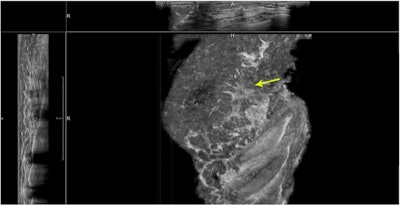

ABUS is primarily designed as a screening tool and has major advantages over handheld ultrasound – other than not dependent on an operator. The technique ensures evaluation of the entire breast in a structured way. Images can be obtained by technicians and read in batch mode by a radiologist. ABUS also enables comparison with prior imaging. It works well for women with dense breasts and provides an overview of the breast, making it useful for extent estimation of larger and more diffuse-growing lesions. However, there are also things to watch out for, such as artifacts, which Dr. Ritse Mann from the radiology department at Radboud University Nijmegen Medical Centre in Nijmegen, the Netherlands, will cover during the session.

ABUS uses a mechanically driven wide-array transducer, which moves over a membrane that compresses the breast, while a woman is imaged in the supine position.

"A first issue is that skin contact might not always be good, despite the use of a large amount of lotion, leading to reverberation artifacts at locations where air bubbles are caught between the skin and the transducer," he said. "Furthermore, respiration causes a sinusoidal wave in the imaged breast tissue, which might distort, in particular, coronal reconstructions of the image."

The ABUS operator cannot align the transducer head relative to the structures within the breast so quite commonly, Cooper's ligaments are hit tangentially by the ultrasound beam, he added. This causes shadowing artifacts below the ligament that seem to move through the breast.

"We refer to these artifacts as 'wandering shadows.' Similarly, due to suboptimal alignment and a suboptimal focal depth, simple cysts often do not appear completely black, and thus resemble small solid lesions," he said.